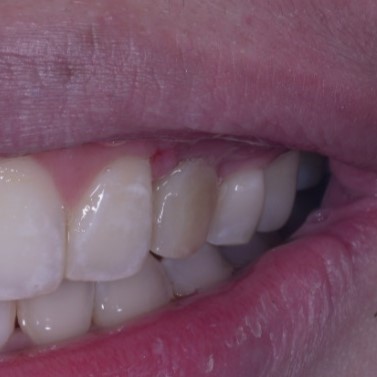

I would be interested to see what an intraoral photo of the implant looks like. I invite you to share if you have one!

Hello Ivan, thank you for your reassurance. Here are some of the post operative one week photos. Good thing is patient has a low lip line. And yes, I could not relly see any exposure and I did place some bone graft with straumann xenoflex at the apical region. Have a great weekend !

The gingiva biotype looks thick type so, I don’t think you will have problem with the implant